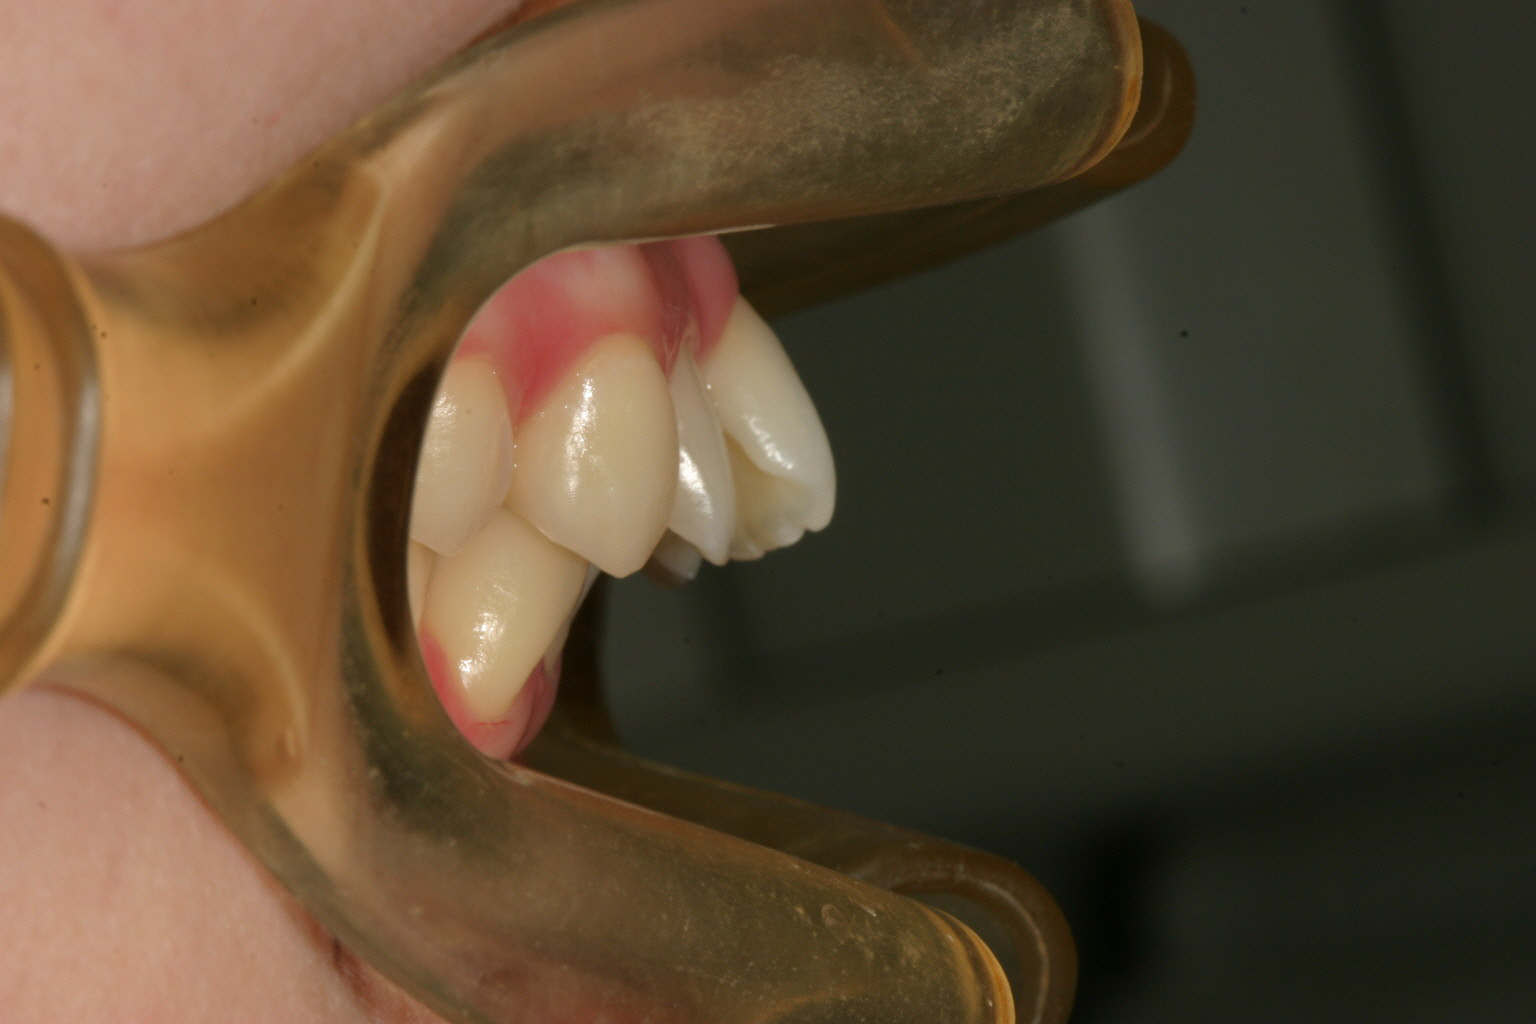

前歯横から見ますとかなりの出っ歯になっています。

抜歯矯正する事無くここまで出っ歯が改善しました。